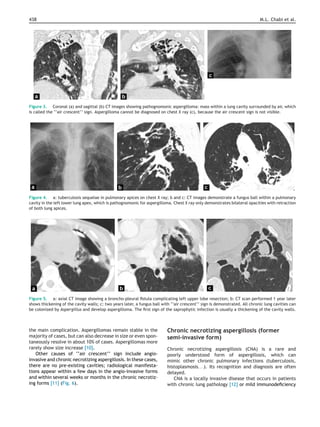

Figure 3. Coronal (a) and sagittal (b) CT images showing pathognomonic aspergilloma: mass within a lung cavity surrounded by air, which

is called the ‘‘air crescent’’ sign. Aspergilloma cannot be diagnosed on chest X ray (c), because the air crescent sign is not visible.

Figure 4. a: tuberculosis sequelae in pulmonary apices on chest X ray; b and c: CT images demonstrate a fungus ball within a pulmonary

cavity in the left lower lung apex, which is pathognomonic for aspergilloma. Chest X ray only demonstrates bilateral opacities with retraction

of both lung apices.

Figure 5. a: axial CT image showing a broncho-pleural fistula complicating left upper lobe resection; b: CT scan performed 1 year later

shows thickening of the cavity walls; c: two years later, a fungus ball with ‘‘air crescent’’ sign is demonstrated. All chronic lung cavities can

be colonized by Aspergillus and develop aspergilloma. The first sign of the saprophytic infection is usually a thickening of the cavity walls.